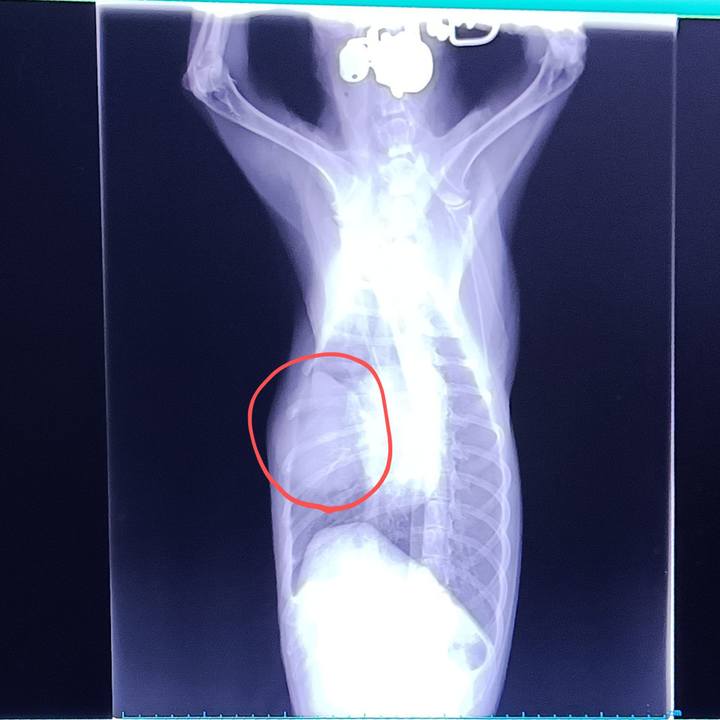

右の胸膜に浸潤、一部外側に盛り上がった#血管肉腫 最初触って僅かな膨らみで気付く